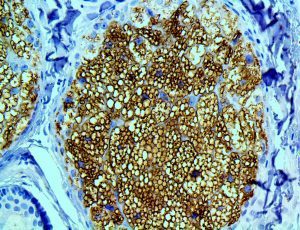

It is the ICU physician who is most likely to witness one of the deadliest manifestations of the abnormal immunological response, the cytokine storm syndrome (CSS). This response is also referred to by some as the cytokine release syndrome (CRS). CSS is characterized by continuous activation and expansion of macrophage and lymphocyte populations, which secrete large amounts of cytokines, causing the cytokine storm. This massive cytokine release is akin to hemophagocytic lymphohistiocytosis (HLH) disease, a syndrome characterized by initial unchecked and persistent activation of cytotoxic T lymphocytes and NK cells.

Clinical and laboratory manifestations of HLH include fever, enlarged liver and/or spleen, neurologic dysfunction, coagulopathy, liver dysfunction, cytopenias (i.e., low levels of erythrocytes, leukocytes, and/or platelets), hypertriglyceridemia, hyperferritinemia, hemophagocytosis, and eventually diminished NK cell activity as the immune system becomes progressively paralyzed. HLH can be familial (primary HLH) or secondary to another disease process (sHLH), such as rheumatic disease, in which it is referred to as macrophage activation syndrome (MAS, characterized by elevated ferritin).

This activation induces inflammatory monocytes to highly express IL-6, starting a localized and then systemic cascade effect that results in hyperproduction of IL-6, which accelerates the inflammatory process. Because IL-6 also increases vascular permeability, excessive levels cause blood vessels to become very leaky. This, along with clotting factors released from vascular endothelial cells, stimulates the coagulation cascade, resulting in microthrombosis (tiny clots), which leads to ischemia and tissue death of the kidney, intestines, heart, liver, brain and extremities.